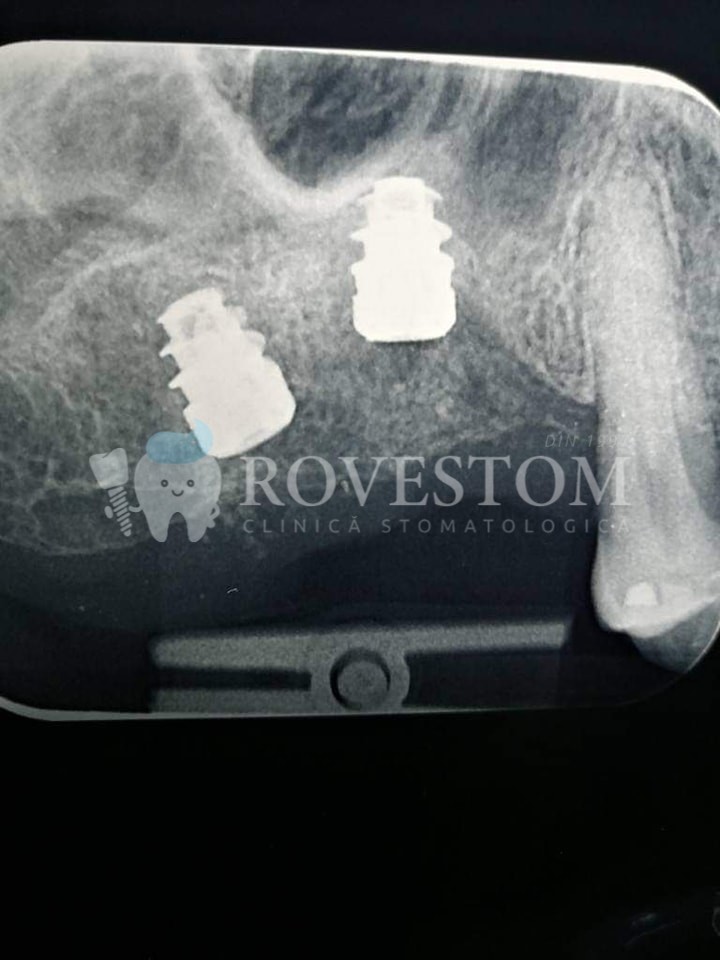

Implantologie